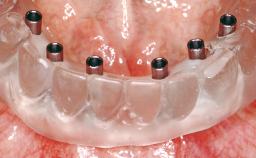

# of Implants 6

Type of Implants One-Piece

Defining Characteristics Fully edentulous upper jaw to be rehabilitated with four or more implants

Modality 6+ implants with immediate loading

Loading Protocol Immediate